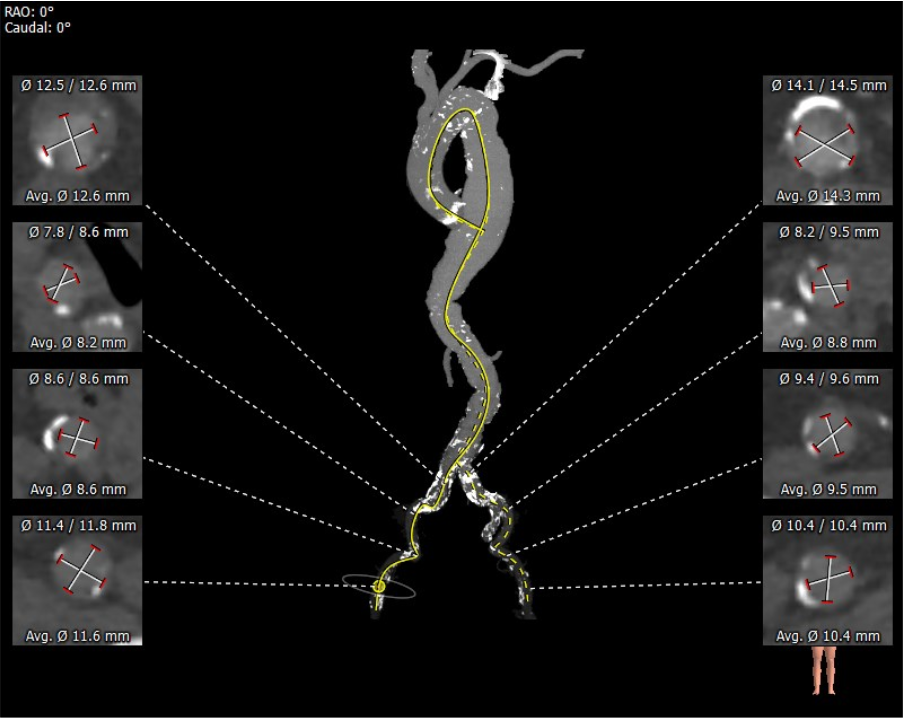

外周分析

• 该患者外周多发附壁血栓,合并胸主、腹主及髂总动脉瘤,动脉瘤巨大,并且内由附壁血栓,经股动脉行TAVR手术血管并发症风险极高。测量发现双侧锁骨下动脉内径可,预计采用左锁骨下动脉为主入路,右股动脉为辅入路。